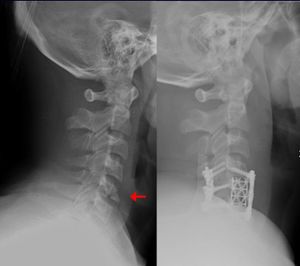

طب العظام يعنى بشكل عام بتصحيح الكسور جراحيا وتجبيرها إضافة إلى عمليات إصلاح وتبديل المفاصل التالفة. بالإضافة إلى أنواع أخرى من العمليات الجراحية التي تعالج أمراض العظام والجهاز الحركي.

جراحة العظام فرع من فروع الطب يعالج اعتلالات العظام والعضلات والأنسجة المتصلة بها. ويُدعى الأطباء الذين يُمارسون جراحة العظام جراحو العظام. وهم يُعالجون مُشكلات طبية كثيرة في هذا المجال منها الكسور، وإصابات الأوتار والأربطة، وتشوهات الأطراف والعمود الفقري. وقد توجد بعض الاعتلالات العظمية منذ الولادة، بينما تظهر اعتلالات أخرى أثناء الطفولة بسبب مشكلات تتعلق بالنمو، أو في فترة متأخرة من العمر نتيجة للشيخوخة. كما تحدث اعتلالات أخرى نتيجة إصابة ما أو مرض. ويُشكل المصابون في حوادث السيارات، أو الأنشطة الرياضية أو أثناء التنزه والاستجمام عددًا كبيرًا من المرضى الذين يعالجهم اختصاصيو العظام. ويصف الأطباء لمعالجة الاعتلالات العظمية الأدوية، والجراحة، والعلاج الطبيعي. وقد يقوم الاختصاصي، على سبيل المثال، بإجراء جراحة لتقويم كسر أو تشوه. وبعد الجراحة قد يستخدم الاختصاصي قالبًا أو مقبضًا، ويصف العلاج الطبيعي كي يساعد على الشفاء. مثل هذه المعالجة قد تشمل استخدام جهاز يطلق نبضات كهربائية تُساعد العظم على الالتئام. كما قد يقوم الاختصاصي بإجراء جراحة لاستبدال مفصل من البلاستيك أو المعدن أو من مواد أخرى بمفصل ملتهب، أو مصاب. والمفصل الذي يستبدل عادة أكثر من غيره، هو مفصل الورك.

- جراحة العمود الفقري